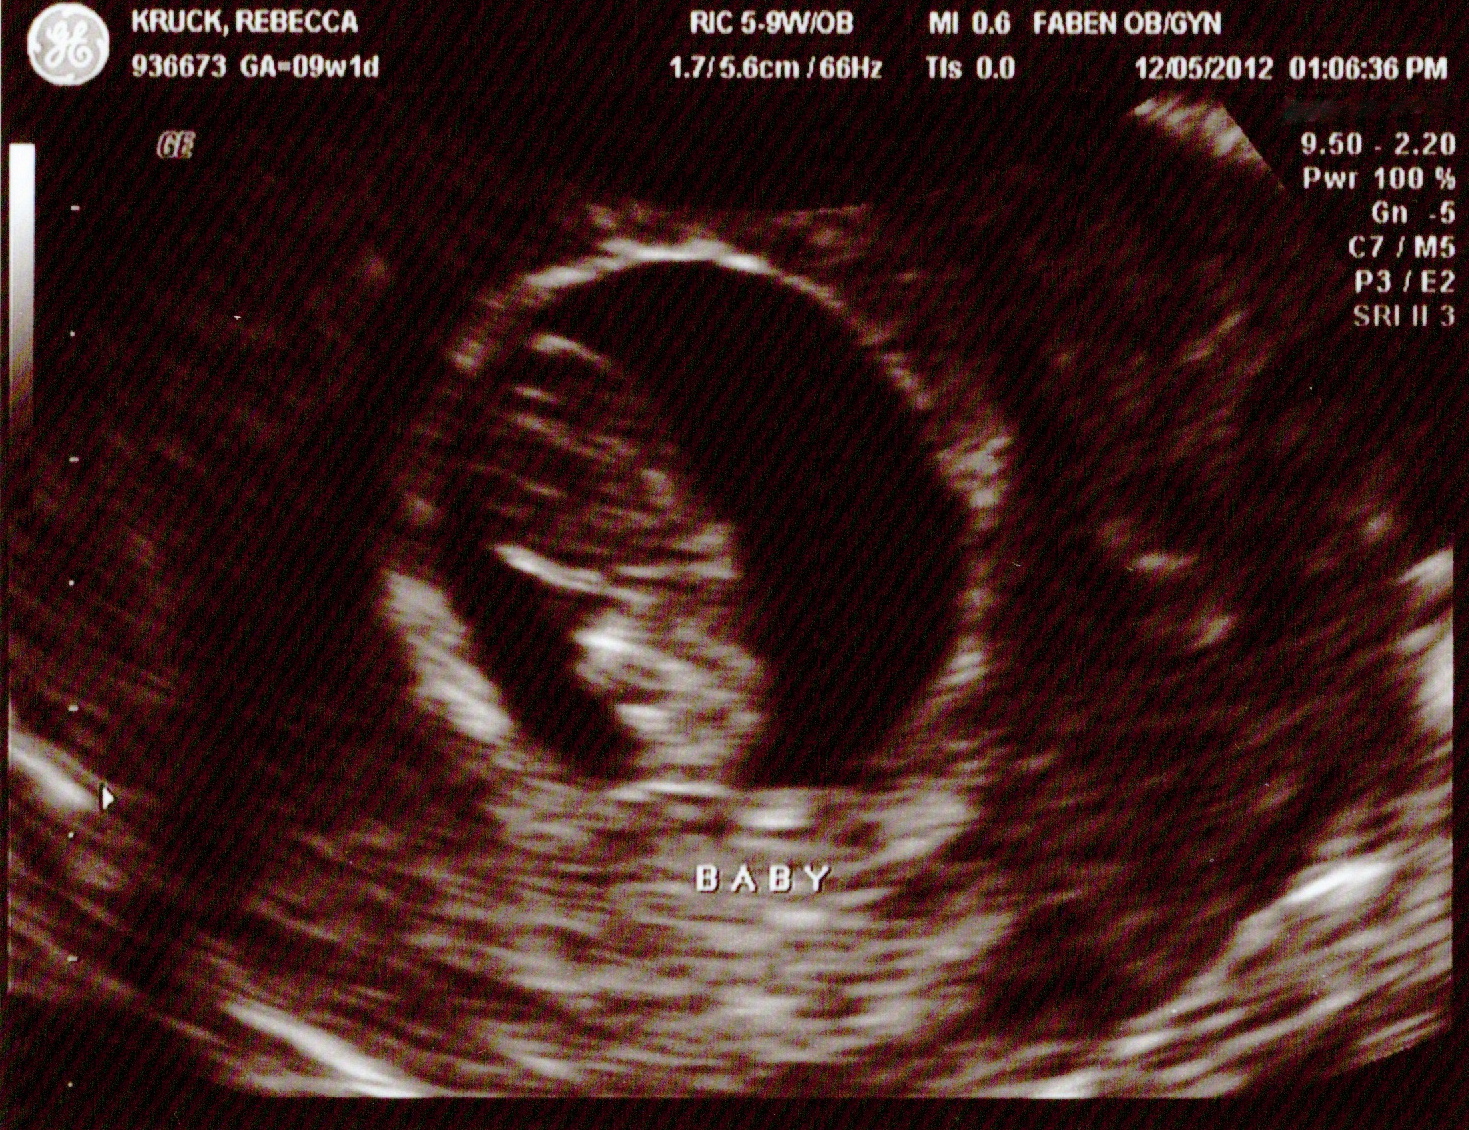

Dan and I found out we were pregnant (unofficially) on Nov. 1, 2012 and (officially) on Dec. 5, 2012. IMAG0903  Baby